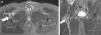

Desgarro de los músculos glúteo menor y medio. Las secuencias en ponderación STIR, planos (a) axial y (b) coronal, detectan la rotura parcial a nivel de la unión miotendinosa distal de ambos músculos. Se observa bursitis intertrocantérea y edema del vientre muscular a predominio del glúteo menor (flechas).

Desgarro del piriforme o piramidal de la pelvis (flecha interna) y glúteo medio (flecha externa) izquierdos. La secuencia ponderada en STIR, plano axial, registra una rotura fascicular de ambos grupos musculares, con marcados signos de edema de partes blandas. La RM, por su amplio campo visual, permite reconocer desgarros de grupos musculares adyacentes de localización profunda.